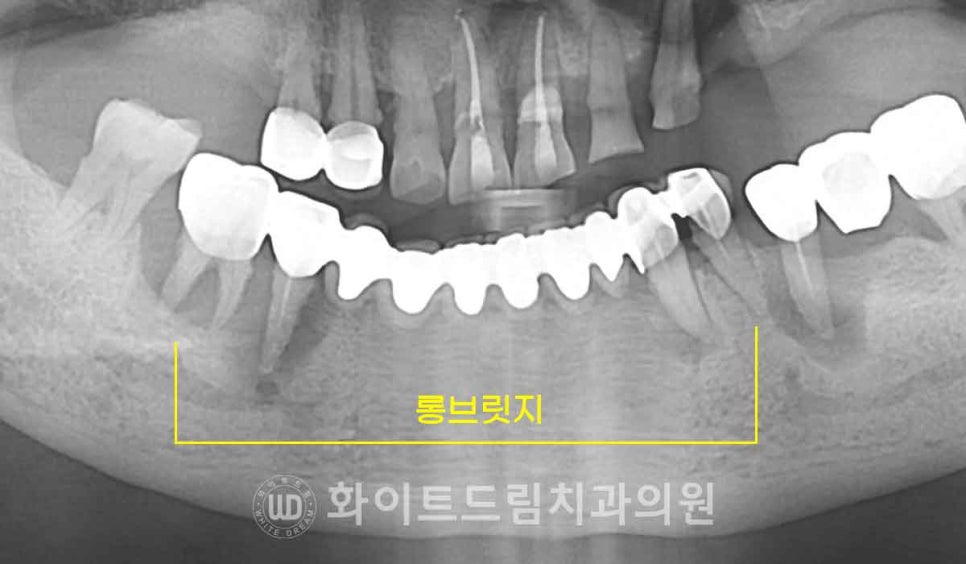

롱브릿지에 대해 잠깐 언급을 하자면

이 롱브릿지는 일반 브릿지(3-4 unit)보다 더 많은 개수의 치아를 보철로

연결해 놓은 것을 말합니다.

▲ 일반적으로 흔히 치료하는 브릿지 치아 개수

여러 치아를 긴 보철물로 묶어주면

결손 부위를 한 번에 수복할 수 있고 치료 비용이 저렴하다는 장점이 있지만

그만큼 지대치에 가해지는 하중이 커져 장기적인 안정성에는 좋지 않습니다.

게다가 여러 치아의 보철이 하나로 묶여있어 비위생적입니다.

음식물이 보철 하방에 굉장히 잘 끼는데 이 부위는 일반 양치질로는

제대로 닦기가 힘듭니다.